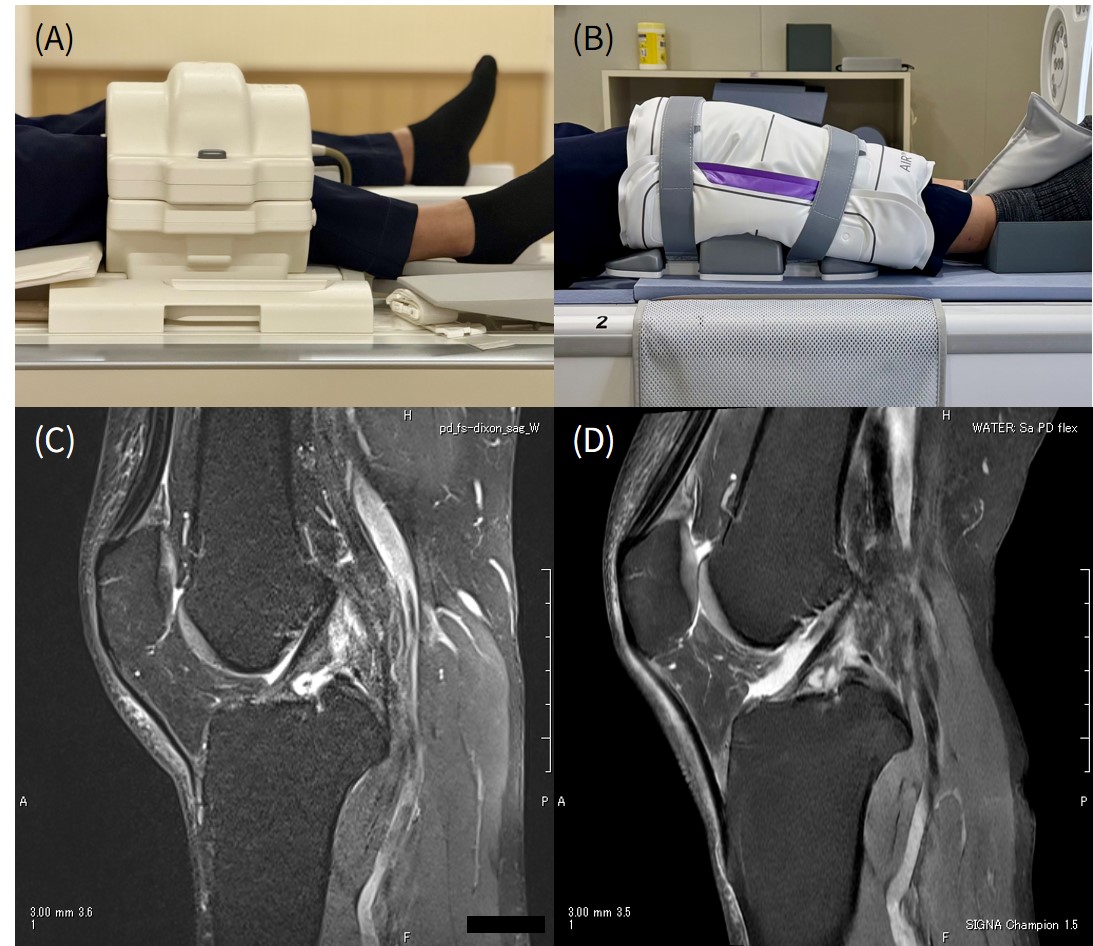

2017年のRSNAで初めて目にしたときから、その自由度の高さに驚きました。体格や部位に合わせて自然にフィットし、カップリングの影響を抑えながら高いSNRを確保できます。特に膝撮像では、従来のコイルでは難しかった「膝を軽く曲げた状態」でも安定した画像が得られるようになり、患者さんの負担も大幅に軽減されました。 (図3)

図3: 前装置とのコイル比較

従来コイル (A) よりもAIR™コイル (B) の方が屈曲しやすく、大腿骨下面とACLを

離して撮りやすい (C, D) ウィンタースポーツが盛んな地域なので、

AIR™コイルの有用性が発揮され、上腕や肘などの使用にも自由度が高い。